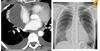

Obstruction of left bronchus Air trapping in left lung - - hyperinflation Mediastinum to the right

78